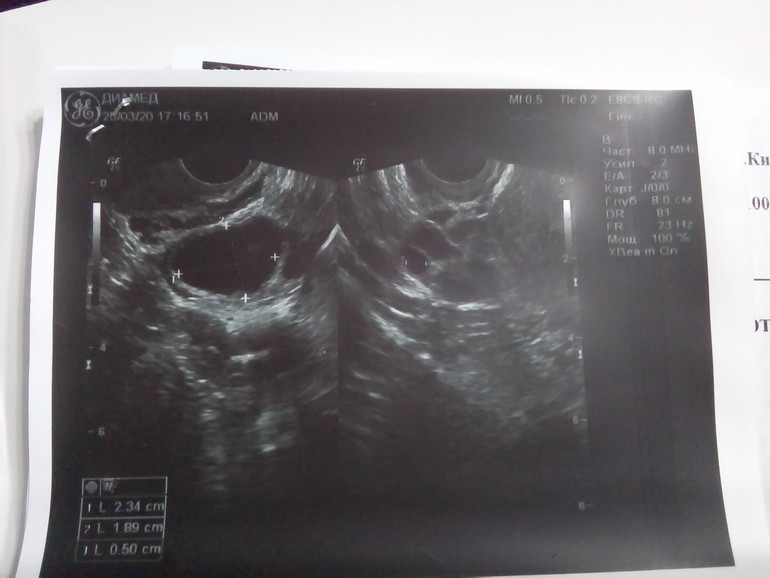

Ниже это ДФ 23*19 мм

Ниже ЖТ 17 мм